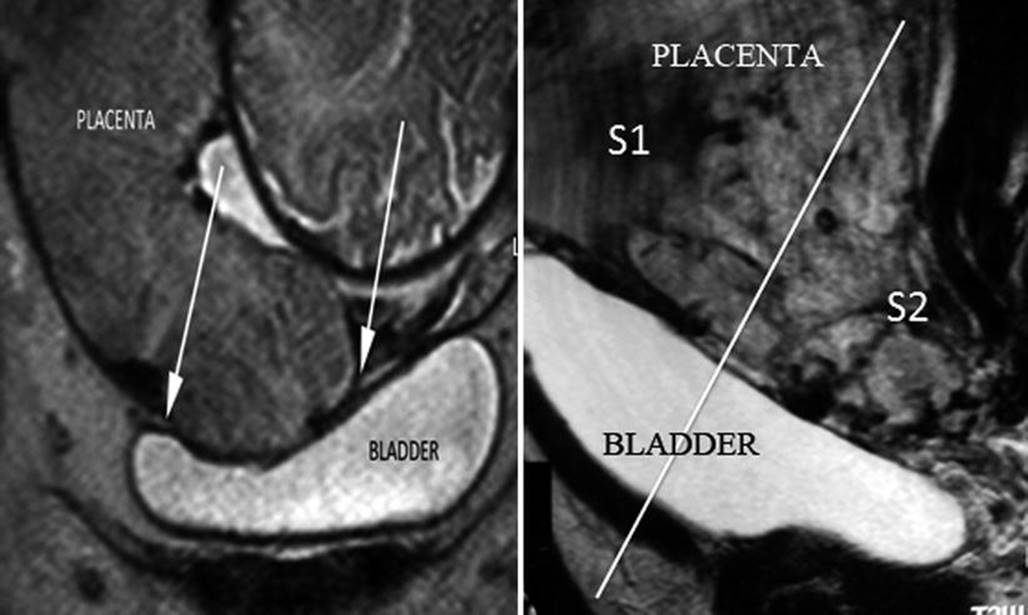

Historically, 2 pedicles have been described for uterine irrigation, the uterine and the ovary arteries. However, after the use of embolisation to manage different types of obstetric haemorrhage, some complications and failures couldn’t be explained according the classic anatomy. A preliminary study made to use a uterine compression device (myomas treatment) demonstrated that lateral compression of uterine tissues above uterine arteries produces uterine necrosis in 6 h [27]. This was the first published study that demonstrated that the upper pedicle (ovary and round ligament artery) is not able to replace the uterine blood flow after uterine artery ligature or embolisation. A few years later, an anatomical study showed a thick and wide communicated anastomosis between vaginal and uterine arteries [28]. Irrigation areas from upper and lower uterine pedicles are different and also their origin. Uterine arteries arise from the anterior division of iliac internal artery, while vaginal ones arise from the posterior division. A practical division of uterine irrigation areas is the peritoneal reflection, which determines area S1 (above peritoneal reflection) and area S2 below this. S1 sector is mainly irrigated by the uterine arteries, while S2 sector by collaterals of the pudendal internal arteries. The topography of placental invasion indicated which is the most effective method for proximal vascular control [29]. For S1 invasions (less frequent in AIP), anterior iliac internal control is effective, but for S2 placental invasions, it is necessary to control the blood flow of the pudendal internal branches and their anastomotic connection, so the most accurate vascular control is the iliac common or aortic vascular control [30].

Identification of S1 and S2 areas can be established by pMRI, sagittal slice (Fig. 14.10). A line that perpendicularly crosses the middle of the posterior bladder wall determines an upper area named S1, which mainly corresponds to the uterine body, and an area below this line, named S2, which involves the lower segment, cervix and upper vagina [9]. Most part of AIP is located in S2 area, which also explained the high rate of failures with the use of uterine or internal iliac vascular control.

Sagittal MRI T2 image: perpendicular plane which divide the posterior bladder wall determine an areas S1 and S2. White arrow shows an interrupted myometrium. Lagoons and vessels are clearly visible in the myometrial-bladder interphase